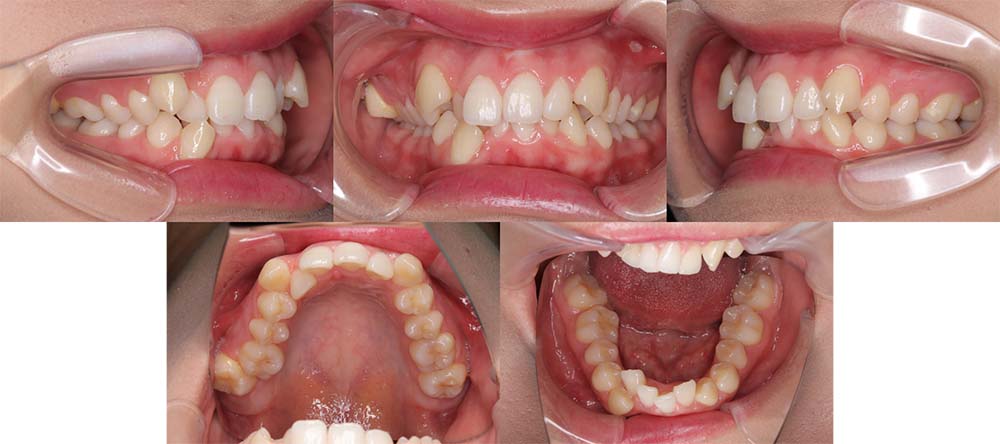

| 症例分類 | 上顎前突、叢生、シザースバイト |

| 診断名 | 右上7のシザーズバイトを伴う上下重度叢生skeletal2 |

| 主訴 | 歯並びが悪くて全体的にガタガタ |

| 年齢 | 19歳11ヶ月 |

| 性別 | 女性 |

| 抜歯部位 | 上顎左右と右下の第一小臼歯、左下の第二小臼歯(4本)、上顎右側第二大臼歯 |

| 使用装置 | 裏側のワイヤー装置 |

| 治療期間 | 2年11ヶ月(5ヶ月程度来院出来ない期間あり) |

| 保定装置 | 固定式保定装置、取り外し式保定装置(8時間) |

| 費用 |

[検査・診断料] ¥49,500 [基本施術料] ¥1,331,000 [調整料] ¥5,500/回 [抜歯] ¥5,500/本 [保定装置] ¥55,000(税込) 抜歯や虫歯治療は他院にて費用が別途かかります。(抜歯¥4,000〜10,000/本)

上下の重度叢生と上の歯が前方にあり上顎両側の第一小臼歯と下顎右側第一小臼歯、下顎左側第二小臼歯、上顎右側第二大臼歯(上顎右側親知らずを咬合に使用)を抜去して上下リンガルで治療を行いました。 左上の第二大臼歯部の咬合が深かったため、一時的に頬側に装置をつけさせて頂きました。裏側に装置を装着すると噛み合わせを浅くするためのバイトアップがかなりの量が必要になり咬みづらくなってしまうためです。

5ヶ月程度来院が出来なかった期間がありましたが、問題なく治療を終了することができました。